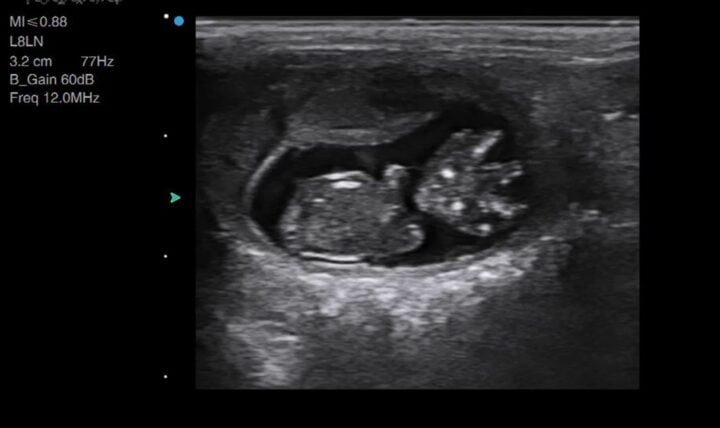

You will likely begin with your depth on its default setting or increased for larger breeds of dog. Once you find a gestation sac (Figure 1), you should optimise your image by reducing your depth and ensuring your focal point is at the level of the foetus. This will allow you to confirm the presence of a heartbeat.